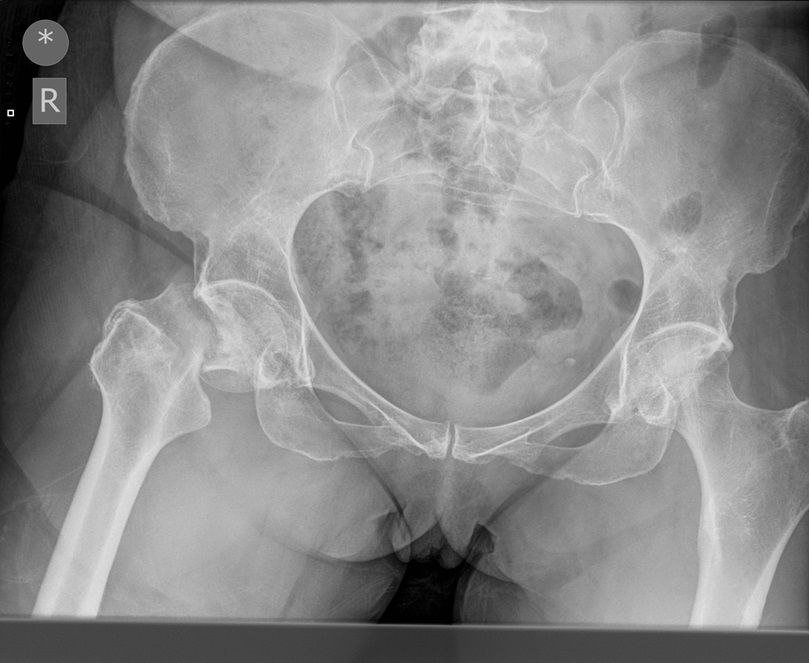

Question 1

Question

Which operation would you chose?

Answer

• THR

• Hemiarthroplasty